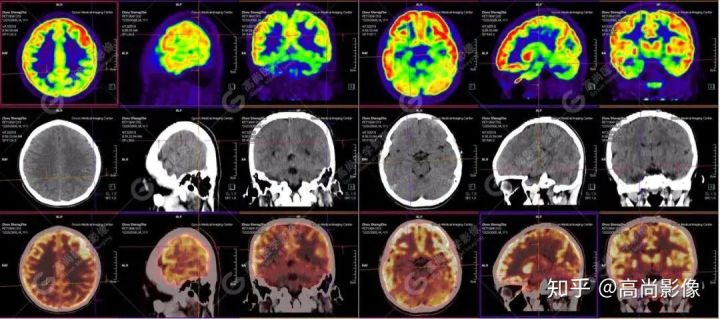

【病史摘要】男性,11歲;9歲時(shí)無(wú)明顯誘因癲癇發(fā)作,發(fā)作時(shí)雙眼上翻,意識(shí)不清,全身抽搐,每年發(fā)作4~5次,近期未行腦電圖及MRI檢查。

【PET/CT 】

提示: 大腦左側(cè)頂葉、顳葉(上部)及右側(cè)額葉、枕葉、顳葉(下部)腦皮質(zhì)代謝廣泛減低,尤以右枕葉為著,多考慮與癲癇發(fā)作相關(guān)。